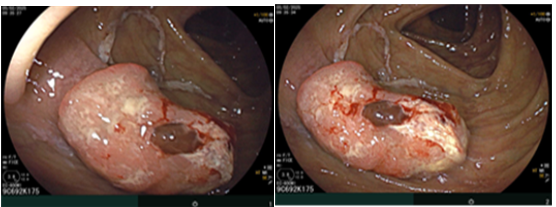

Ca lâm sàng: Ung thư đại tràng ở bệnh nhân 15 tuổi

GS.TS Mai Trọng Khoa; BSNT Hoàng Mạnh Đức, Ths Bùi Quang Lộc , PGS.TS Phạm Cẩm Phương, Bsck II Hoàng Anh, Trung tâm y học hạt nhân và...